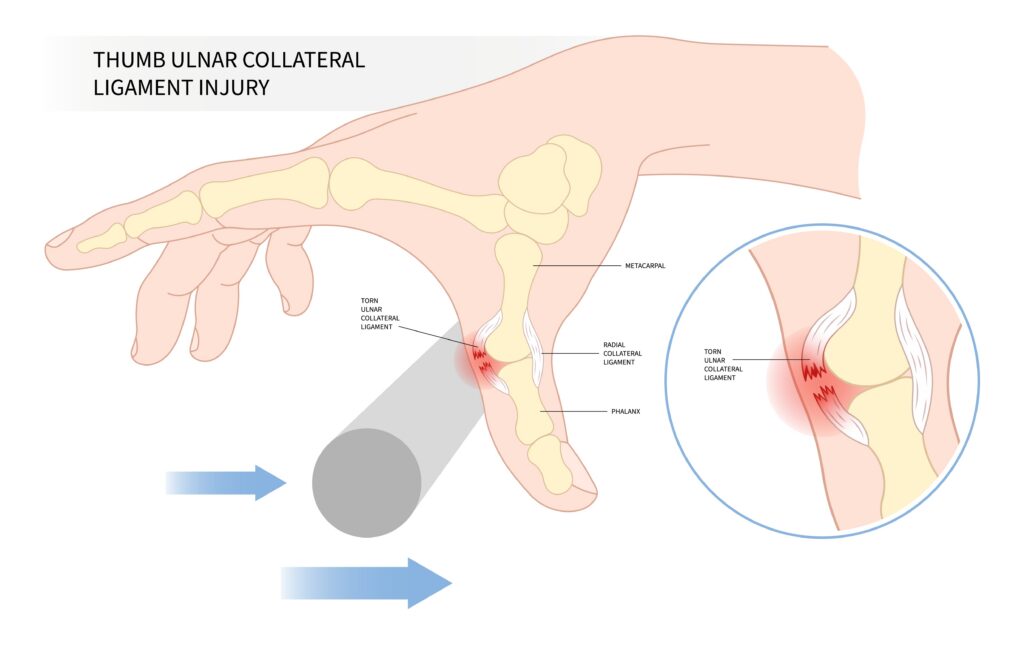

Thumb UCL Injury (Skier’s or Gamekeeper’s Thumb)

These injuries often appear minor but can significantly affect hand function.

The typical mechanism involves forced abduction of the thumb, often during a fall or sports injury.

Patients usually report pain and swelling around the MCP joint of the thumb. X-rays may show a small avulsion fracture, but imaging may also be normal.

The underlying issue is injury to the ulnar collateral ligament of the thumb MCP joint.

Key things to assess

- MCP joint stability (hold the metacarpal head in one hand and the proximal phalanx in the other)

- Test the unaffected side to compare stability

- Pain along the ulnar aspect of the thumb

- Mechanism of injury

If the ligament is completely torn, the thumb becomes unstable and grip strength can be significantly affected.

If you suspect this injury, the patient should be placed in a thumb spica splint and evaluated by hand surgery.